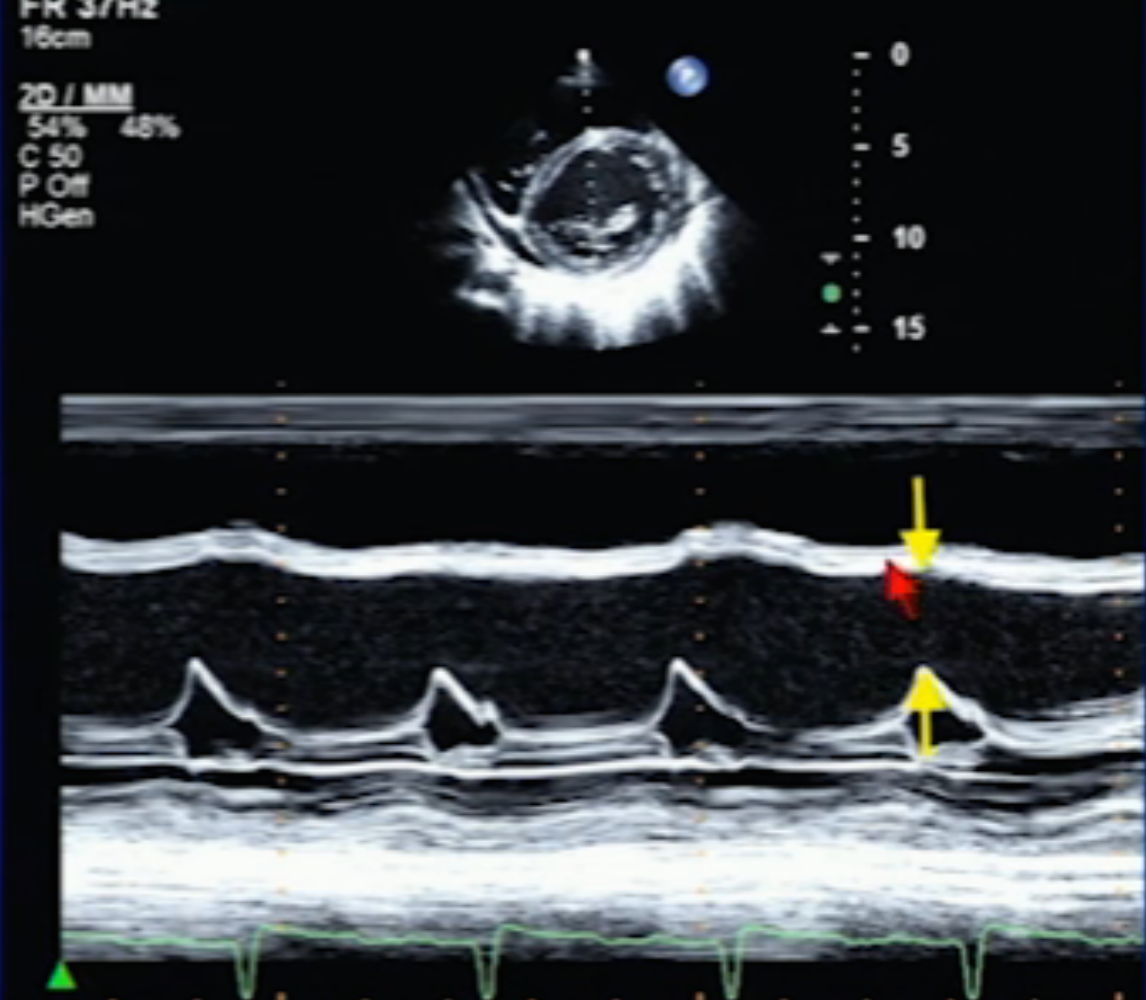

Diagnosis?

DCM

(Large E-point Septal Separation (EPSS))

E-point Septal Separation above which is abnormal (suggesting DCM). When is EPSS not valid?

>10mm

not valid with valvular dz like MS/AR.